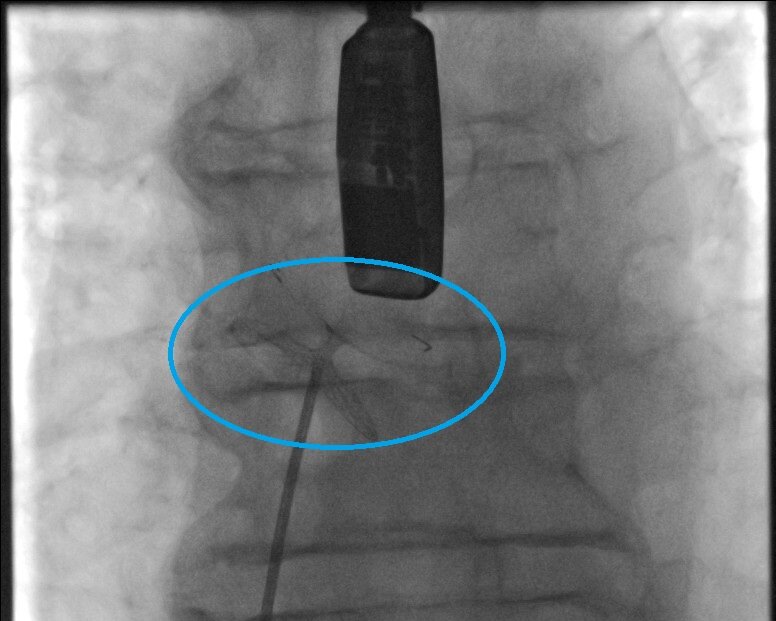

Mit einem rund 30-minütigen minimal-invasiven kardiologischen Eingriff ist es möglich, dieses Loch bei schlagendem Herzen zu schließen. „Der Operateur bringt bei diesem Eingriff einen Katheter über die Leistenvene durch das zu verschließende PFO in den linken Herzvorhof des Patienten. Im Gegensatz zu einer klassischen Herz-OP muss in diesem Fall nicht der Brustkorb geöffnet werden“, so Chefarzt Fürnau.